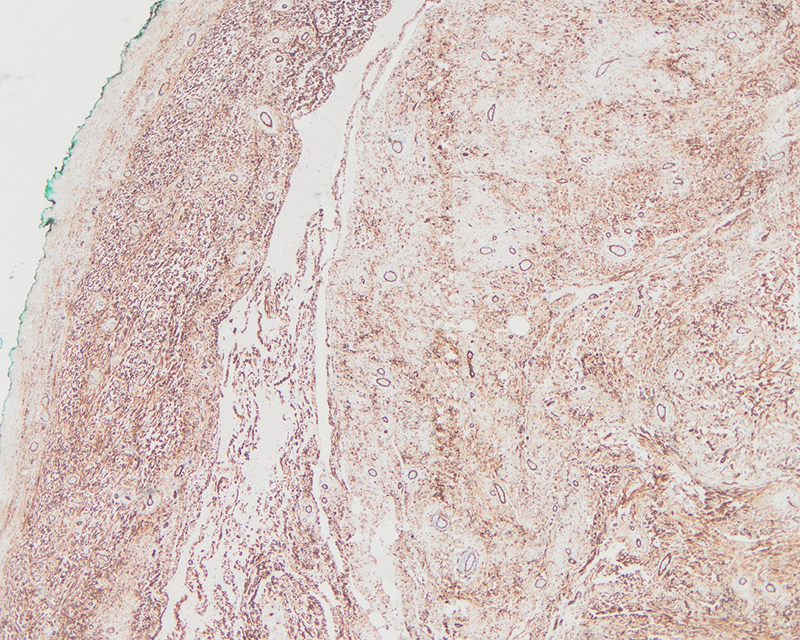

Complete surgical resection of the tumor revealed a well-circumscribed tan-white mass that measured up to 2 cm in greatest dimension. The cut surface was tan-white and firm without evidence of hemorrhage or necrosis. Microscopically, the lesion demonstrated prominent vasculature, pseudovascular spaces, and bland spindle cells in short fascicles with focal mild atypia (Figure 1 and 2). Intralesional fat was present (Figure 3). The lesion showed overall circumscription, with some irregular nodular extensions/prolongations of the lesion into the adjacent soft tissue resulting in the microscopic appearance of satellite lesions. Immunohistochemistry revealed strong CD34 positivity (Figure 4). Estrogen and progesterone receptors were weakly positive and desmin, SMA, and S-100 were negative.